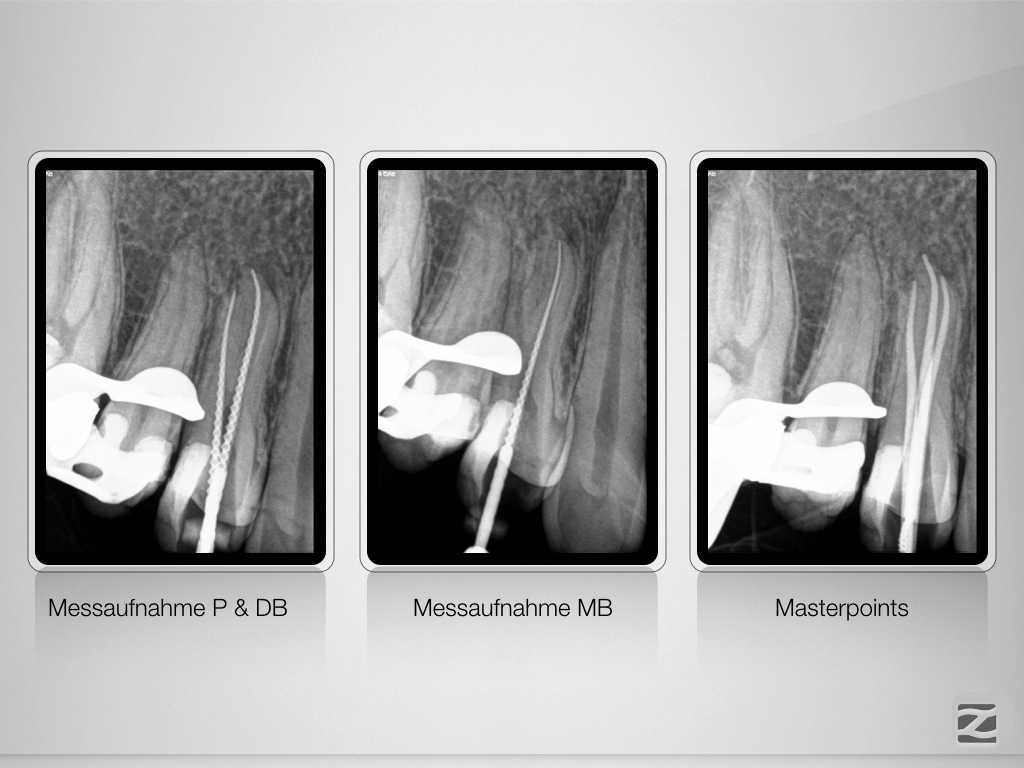

14D.011

Schöner Dreier